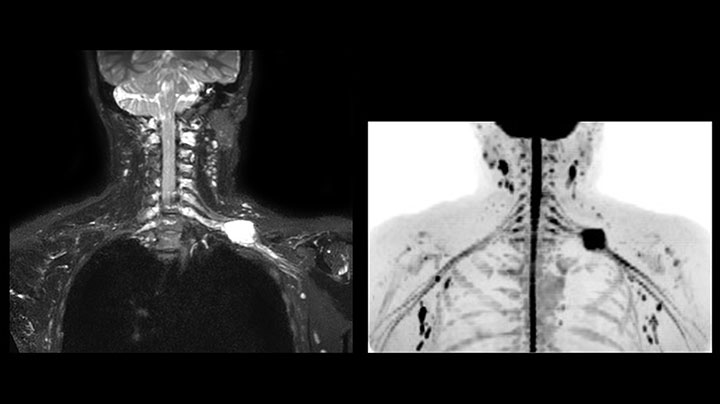

Although the area between the neck and the top of the lung is one of the most difficult areas for MRI, Prodiva 1.5T images show good quality in this 56-year-old male with Pancoast tumor on the right. mDIXON TFE images shows excellent fat suppression in the neck area and the DWI shows almost no distortion.